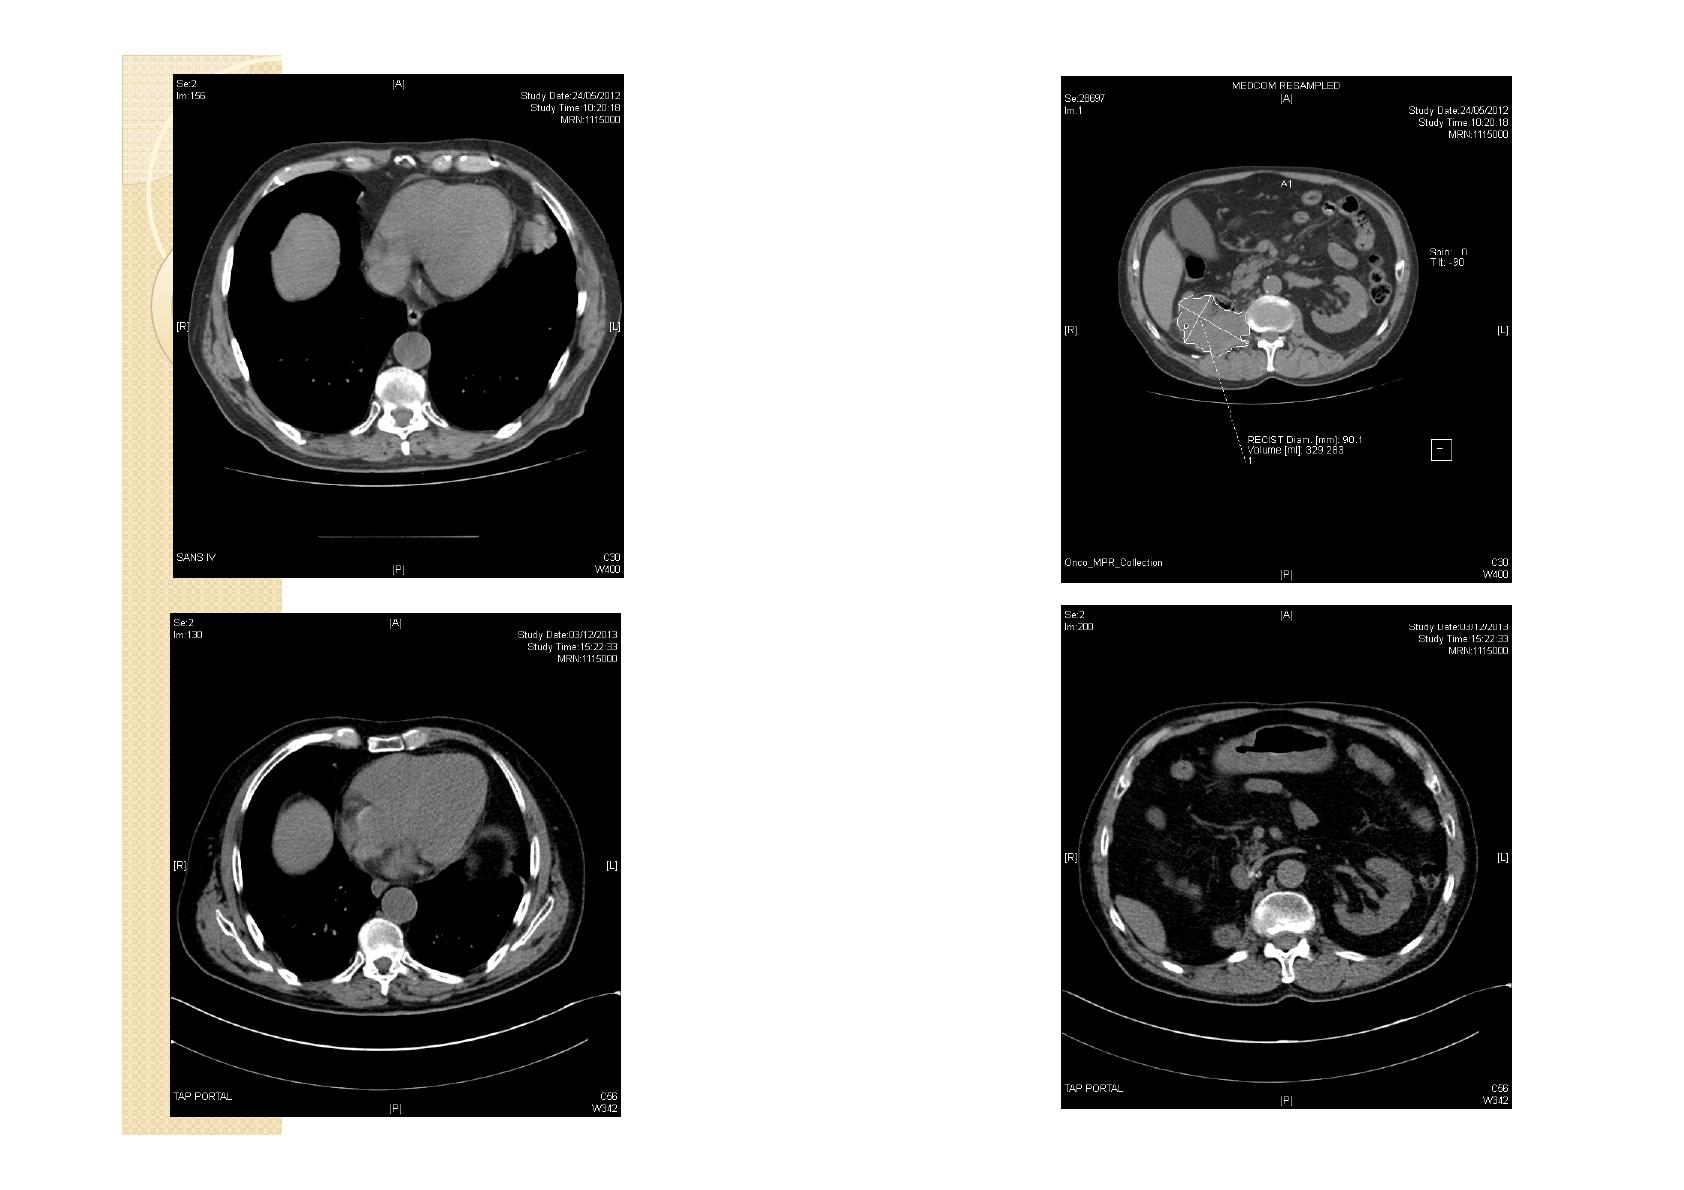

◦Asthénie majeure rythmée par la prise du SUTENT.